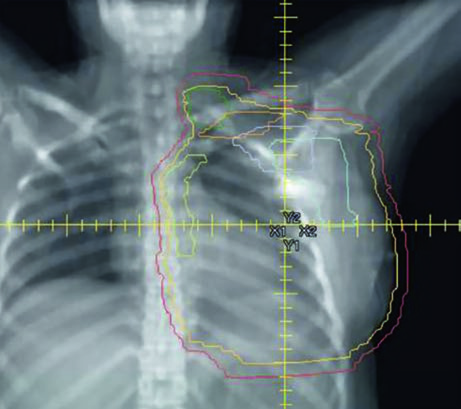

Reconstructed (Tissue Expander) Left Chest Wall

When the patient has tissue expander reconstruction, the planning geometry changes significantly. The expander protrudes the chest wall anteriorly, altering target depths and the spatial relationship with OARs. On the left side, the heart assumes a relatively more anterior position, requiring careful optimization. Figure 12.4 clearly shows the cardiac contour (yellow) in relation to the PTV in the sagittal view — this proximity explains the laterality-specific dosimetric limits.